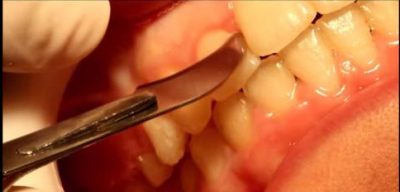

חיתוך סיבים

פעולה ניתוחית בה חותכים את הסיבים השטחיים שמחברים בין השן והחניכיים במטרה להקטין את הנטייה לחזרתה של השן למקומה המקורי לפני התזוזה האורתודונטית.